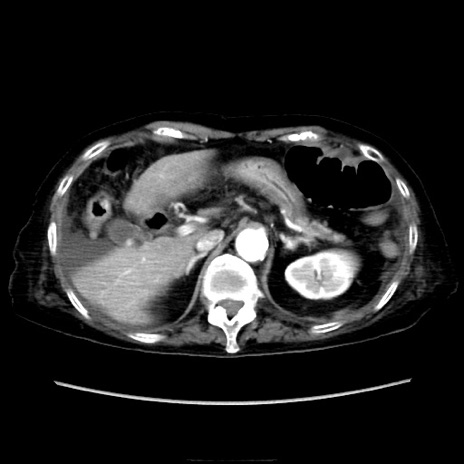

症例40(横断像)

横断像